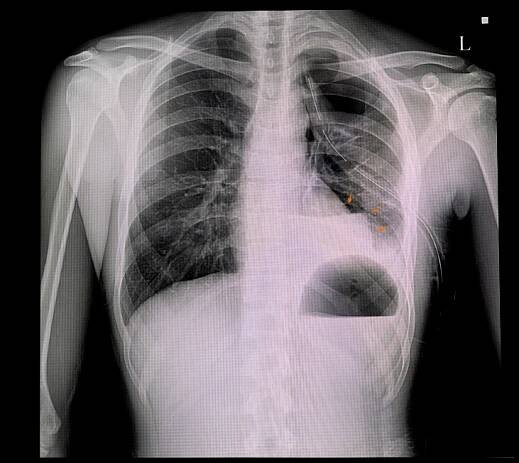

Rentgenový snímek – pneumotorax levé plíce a nahromadění vzduchu v pleurální dutině hrudníku (bílá barva). Zdroj: Getty Images

Pneumotorax - RTG | Medicína, nemoci, studium na 1. LF UK